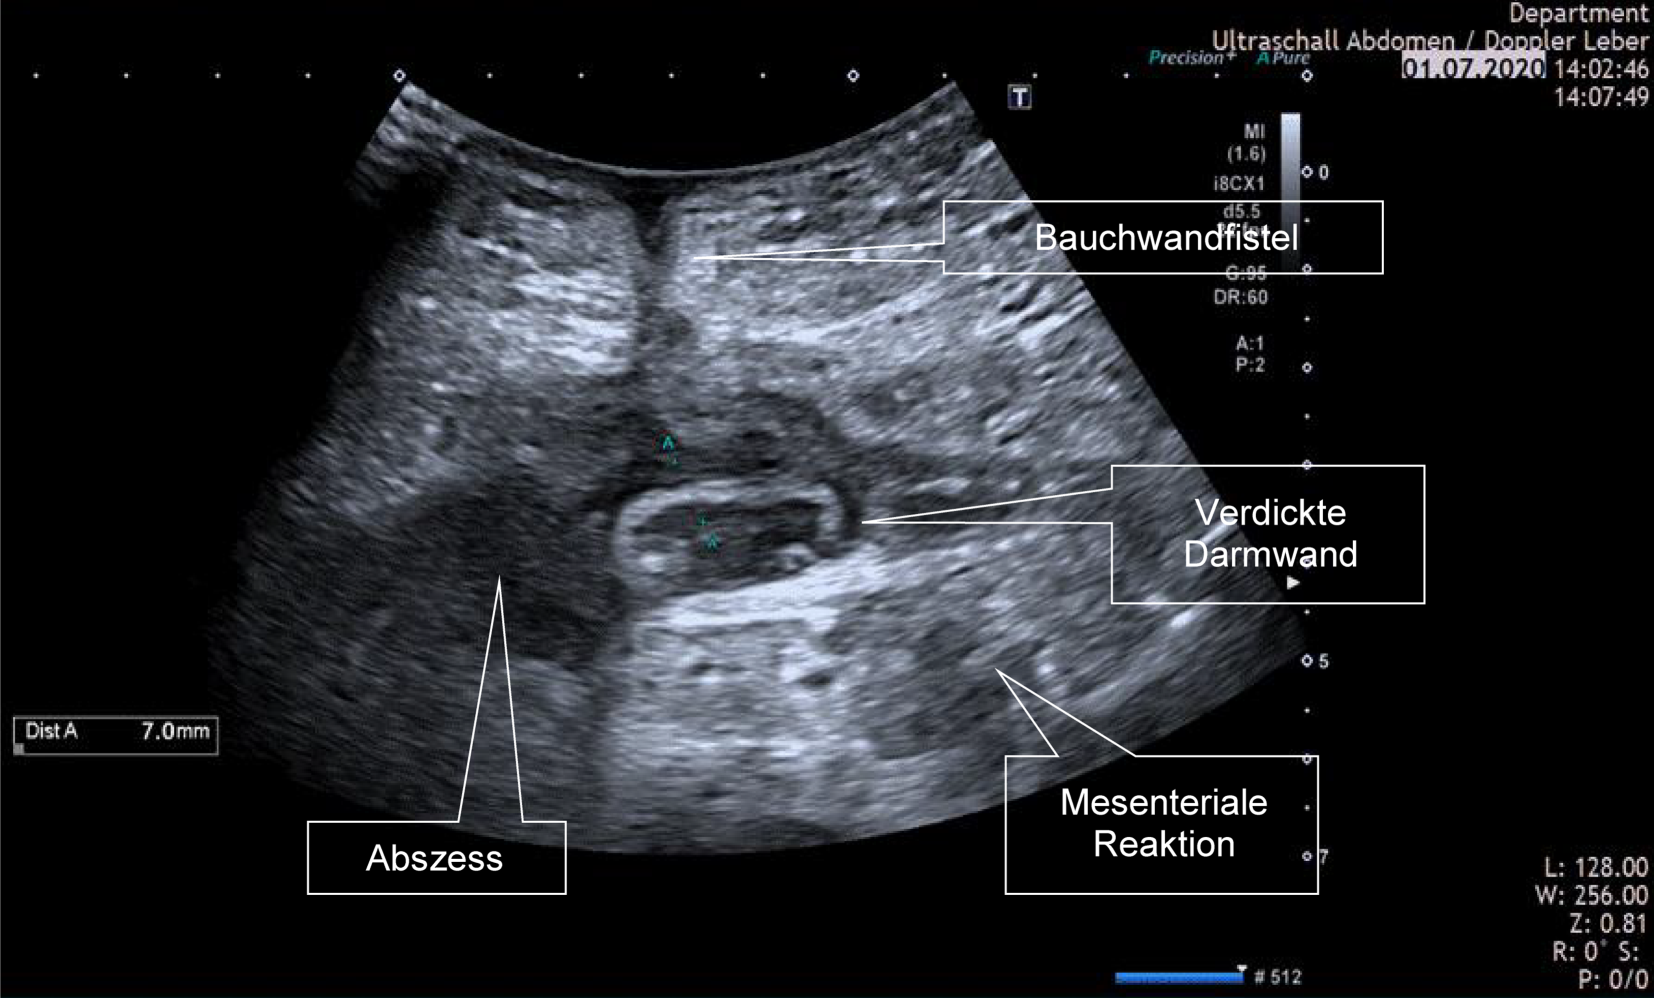

Abb. 6

Nachweis des postoperativen Rezidivs und von Komplikationen. 27-jähriger Patient 6 Monate nach erweiterter Ileozökalresektion mit Teilkolektomie und linksseitiger ileokolischer Anastomose, postoperativer Gewichtsabnahme von 25 kg und einer Sekretion aus der medianen Laparatomie-Narbe. Es zeigt sich eine Darmwandverdickung des neoterminalen Ileums als Zeichen eines postoperativen Rezidivs, um diese Schlinge freie Flüssigkeit, ein echoarmer Gang zur Bauchdecke im Sinne einer Fistel und ein Abszess im Mesenterium

Bild vergrößern